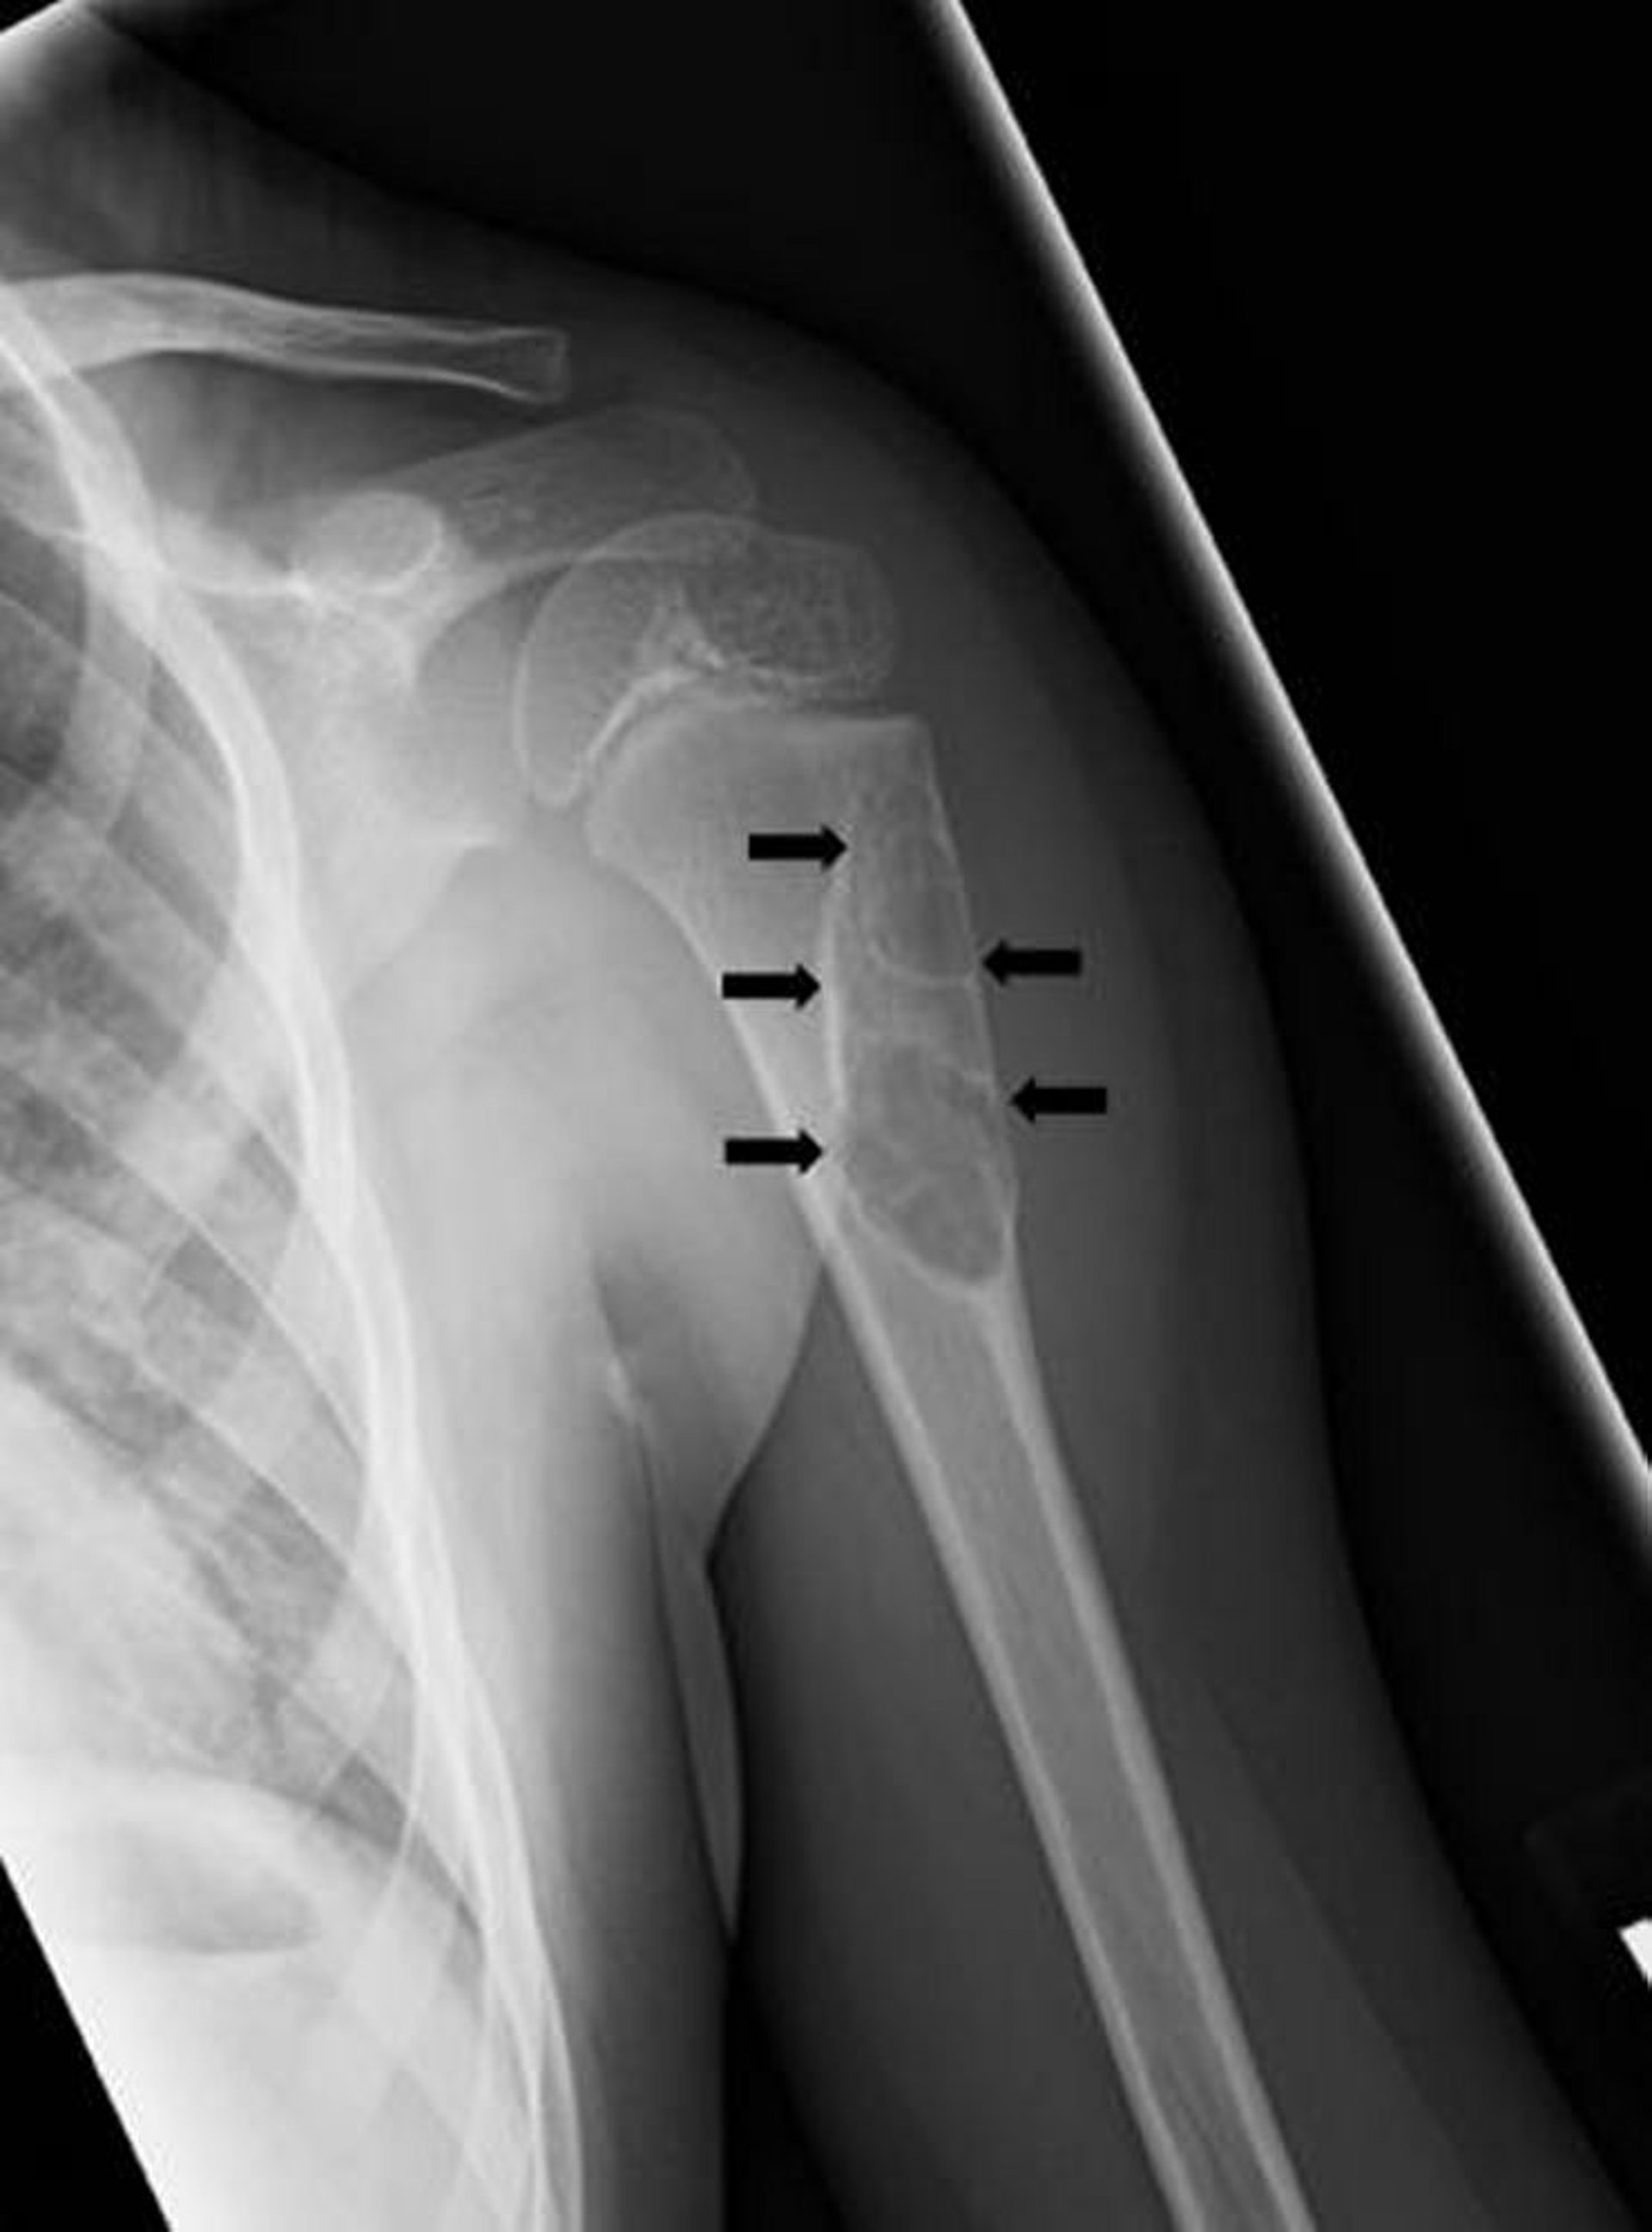

Einfache Knochenzyste

Auf dieser Röntgenaufnahme ist eine einfache, einkammerige Knochenzyste (Pfeile) im Oberarmknochen zu sehen.

Bild mit freundlicher Genehmigung von Dr. med. Michael J. Joyce und Dr. med. Hakan Ilaslan.